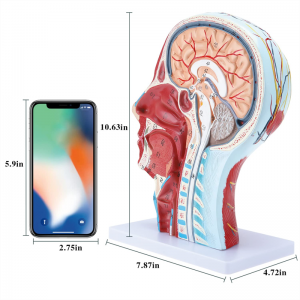

| Iwọn | 21 * 12 * 27cm |

Ni 1: 1 LIGESED】 Mediani Akan Media ti 1: 1 ori nla ti o tobi julọ & ade nla ti iṣan iṣan ti iṣan ti o ni iṣan iṣan. Iṣẹ adaṣe daradara. Nfunni ni kikun ti awọn ẹya anatomical.

Awoṣe iṣan iṣan】 alaye ti o ga pupọ, awọn nọmba ti samisi, jinlẹ ti awọn iṣan to loye awọn iṣan ati ọrun inu & ọrùn ti ori & ọrun. Atter-mq-iṣọn, buluu-vening, alawọ ofeefee.